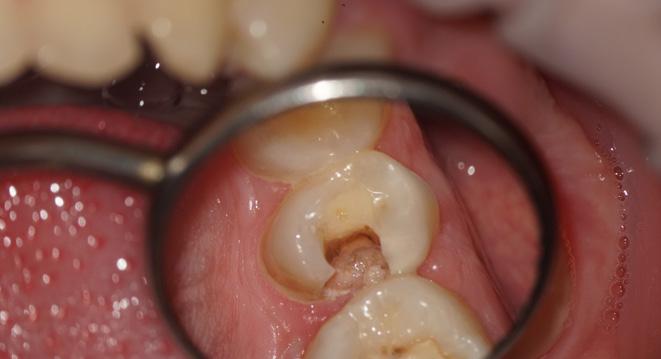

One of the suitable indications for FRC is the endodontically treated premolar with one big orifice and one large oval canal or deep furcation (Figs. 1-4). In such cases, an FRC can be placed as a Nayyar’s core modification5 without preparing the orifice part with Gates or Largos. The restoration can be finished as usual, directly with a conventional composite.

Fig. 1: Pre-operative situation with large orifice.